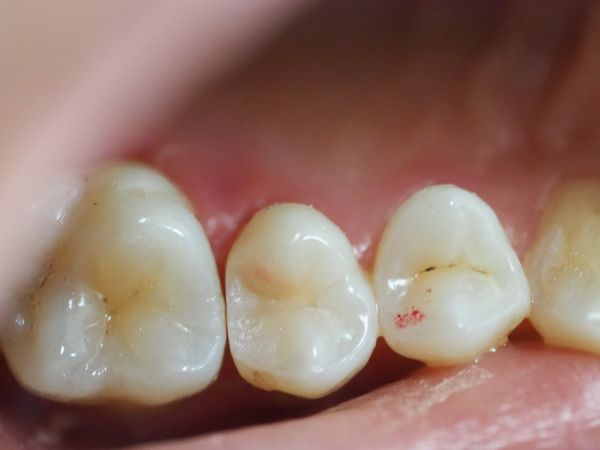

- восстановили анатомическую форму зуба с помощью светоотверждаемой пломбы (края пломбы чётко прилегали к стенкам зуба).

Весь процесс контролировался прицельными снимками RVG (радиовизиографией).